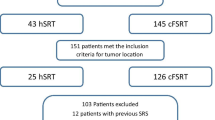

We selected all the meningioma patients who received radiation treatment in our centre from 2000 until 2013. Out of 247 patients, those with previous radiation therapy for head malignancies and those with incomplete planning data or missing clinical data were excluded. Finally 213 patients entered the study.

Median total prescribed dose in all patients were 54 Gy (15–60 Gy). Doses per fraction ranged from 1.75 to 17 Gy and the number of fractions ranged between 1 and 31. The details about delivered doses to PTV and OARs in Suppl. 5. Dose distributions in neuro-optic structures (V45, V50, V54 and V60) are shown in Suppl. 6. These parameters could be calculated only for those patients treated with one plan (n = 187). Dmax values were >54 Gy in 147 OARs, Dmed values exceeded 54 Gy in 7 OARs (Table 3). In order to reduce uncertainties growing from largely different dose/fraction, patients with less than 5 fractions were excluded from further analysis. We subsequently analyzed the remaining 190 patients, whether specific tumor locations were related to higher Dmax values (Table 4). Briefly, meningiomas located within the cavernous sinus, at the skull base, the sphenoid wing, the optic nerve sheath, the sella and at the middle cranial fossa were significantly associated with higher Dmax values, at least in one of the neuro-optic OARs. As an internal control, involvement of neuro-optic OARs into the PTV was also significantly associated with higher Dmax values.

We subsequently investigated, whether treatment techniques had an influence on Dmed- and Dmax-value within neuro-optic OARs. Also for this analysis, RS-cases were excluded. Intriguingly, 3D-planning was associated with significantly lower Dmed within the left optic nerve (p = 0.038), while Dmax did not significantly differ. Dmax values of more than 54 Gy (EQD2) were more likely when 3D planning was used (Fig. 1).